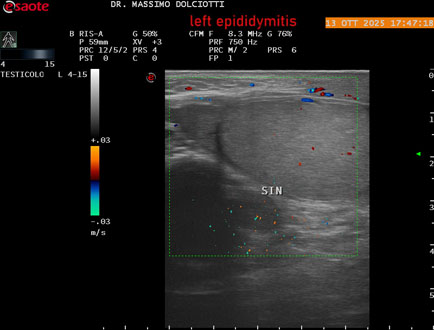

Data inserimento: 14/10/2025

Ecografia del: 13/10/2025

Strumento: Esaote MyLab Eight

Sonda: Lineare Multifrequenza 4-15 MHz

Età Paziente: M 70 anni

Motivazione dell'esame: da 2 giorni dolore al testicolo sinistro.

Commento all'esame: le immagini ed il video documentano l'epididimo sinistro spiccatamente aumentato di volume e di vascolarizzazione, come da flogosi. Didimo sinistro lievemente aumentato di volume. Quadro clinico ed ecografico da ricondurre ad epididimite acuta sinistra.

Conclusioni: epididimite acuta sinistra (acute left epididymitis).

Presentazione: Dr. Massimo Dolciotti - Ancona